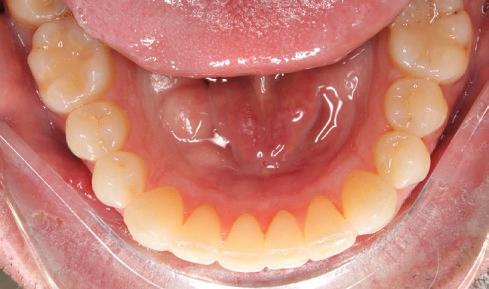

(Full orthodontic treatment cost: $4,200)

For information, visit www dentistry

UBC Dentistry is screening patients

of age and

who require Braces

ubc.ca/gradortho Graduate Orthodontics Program To arrange a screening appointment: Call between 8:30 am – 4 pm (Monday to Friday) 604-827-4991 or email gradorthoclinic@dentistry.ubc.ca T H E U N I V E R S T Y O R B R I T S H C O L U M B A UBC Dentistry is screening patients 7yearsofageandolderwhorequire Braces (Full orthodontic treatment cost: $1,000to$4,200) For information, visit wwwdentistryubcca/gradortho GraduaeOrhodon csProgram Toarrangeascreeningappointment: 604-827-4991(12years&older) 604-827-0706(7to10yearsold) oremailgradorthoclinic@dentistryubcca HEALTHY CHOICES MADE SIMPLE NUTRITION TOURS ARE BACK! Sign up for a FREE nutrition tour personalized to your needs with the Choices Nutrition Team in-store or online at choicesmarkets.com PLANT-BASED GLUTEN-FREE ANTI-INFLAMMATORY GUT-FRIENDLY 100% BC OWNED AND OPERATED VANCOUVER | NORTH VANCOUVER BURNABY SOUTH SURREY ABBOTSFORD KELOWNA COMING SOON TO PARKSVILLE! THANK YOU FOR RECYCLING THIS NEWSPAPER.